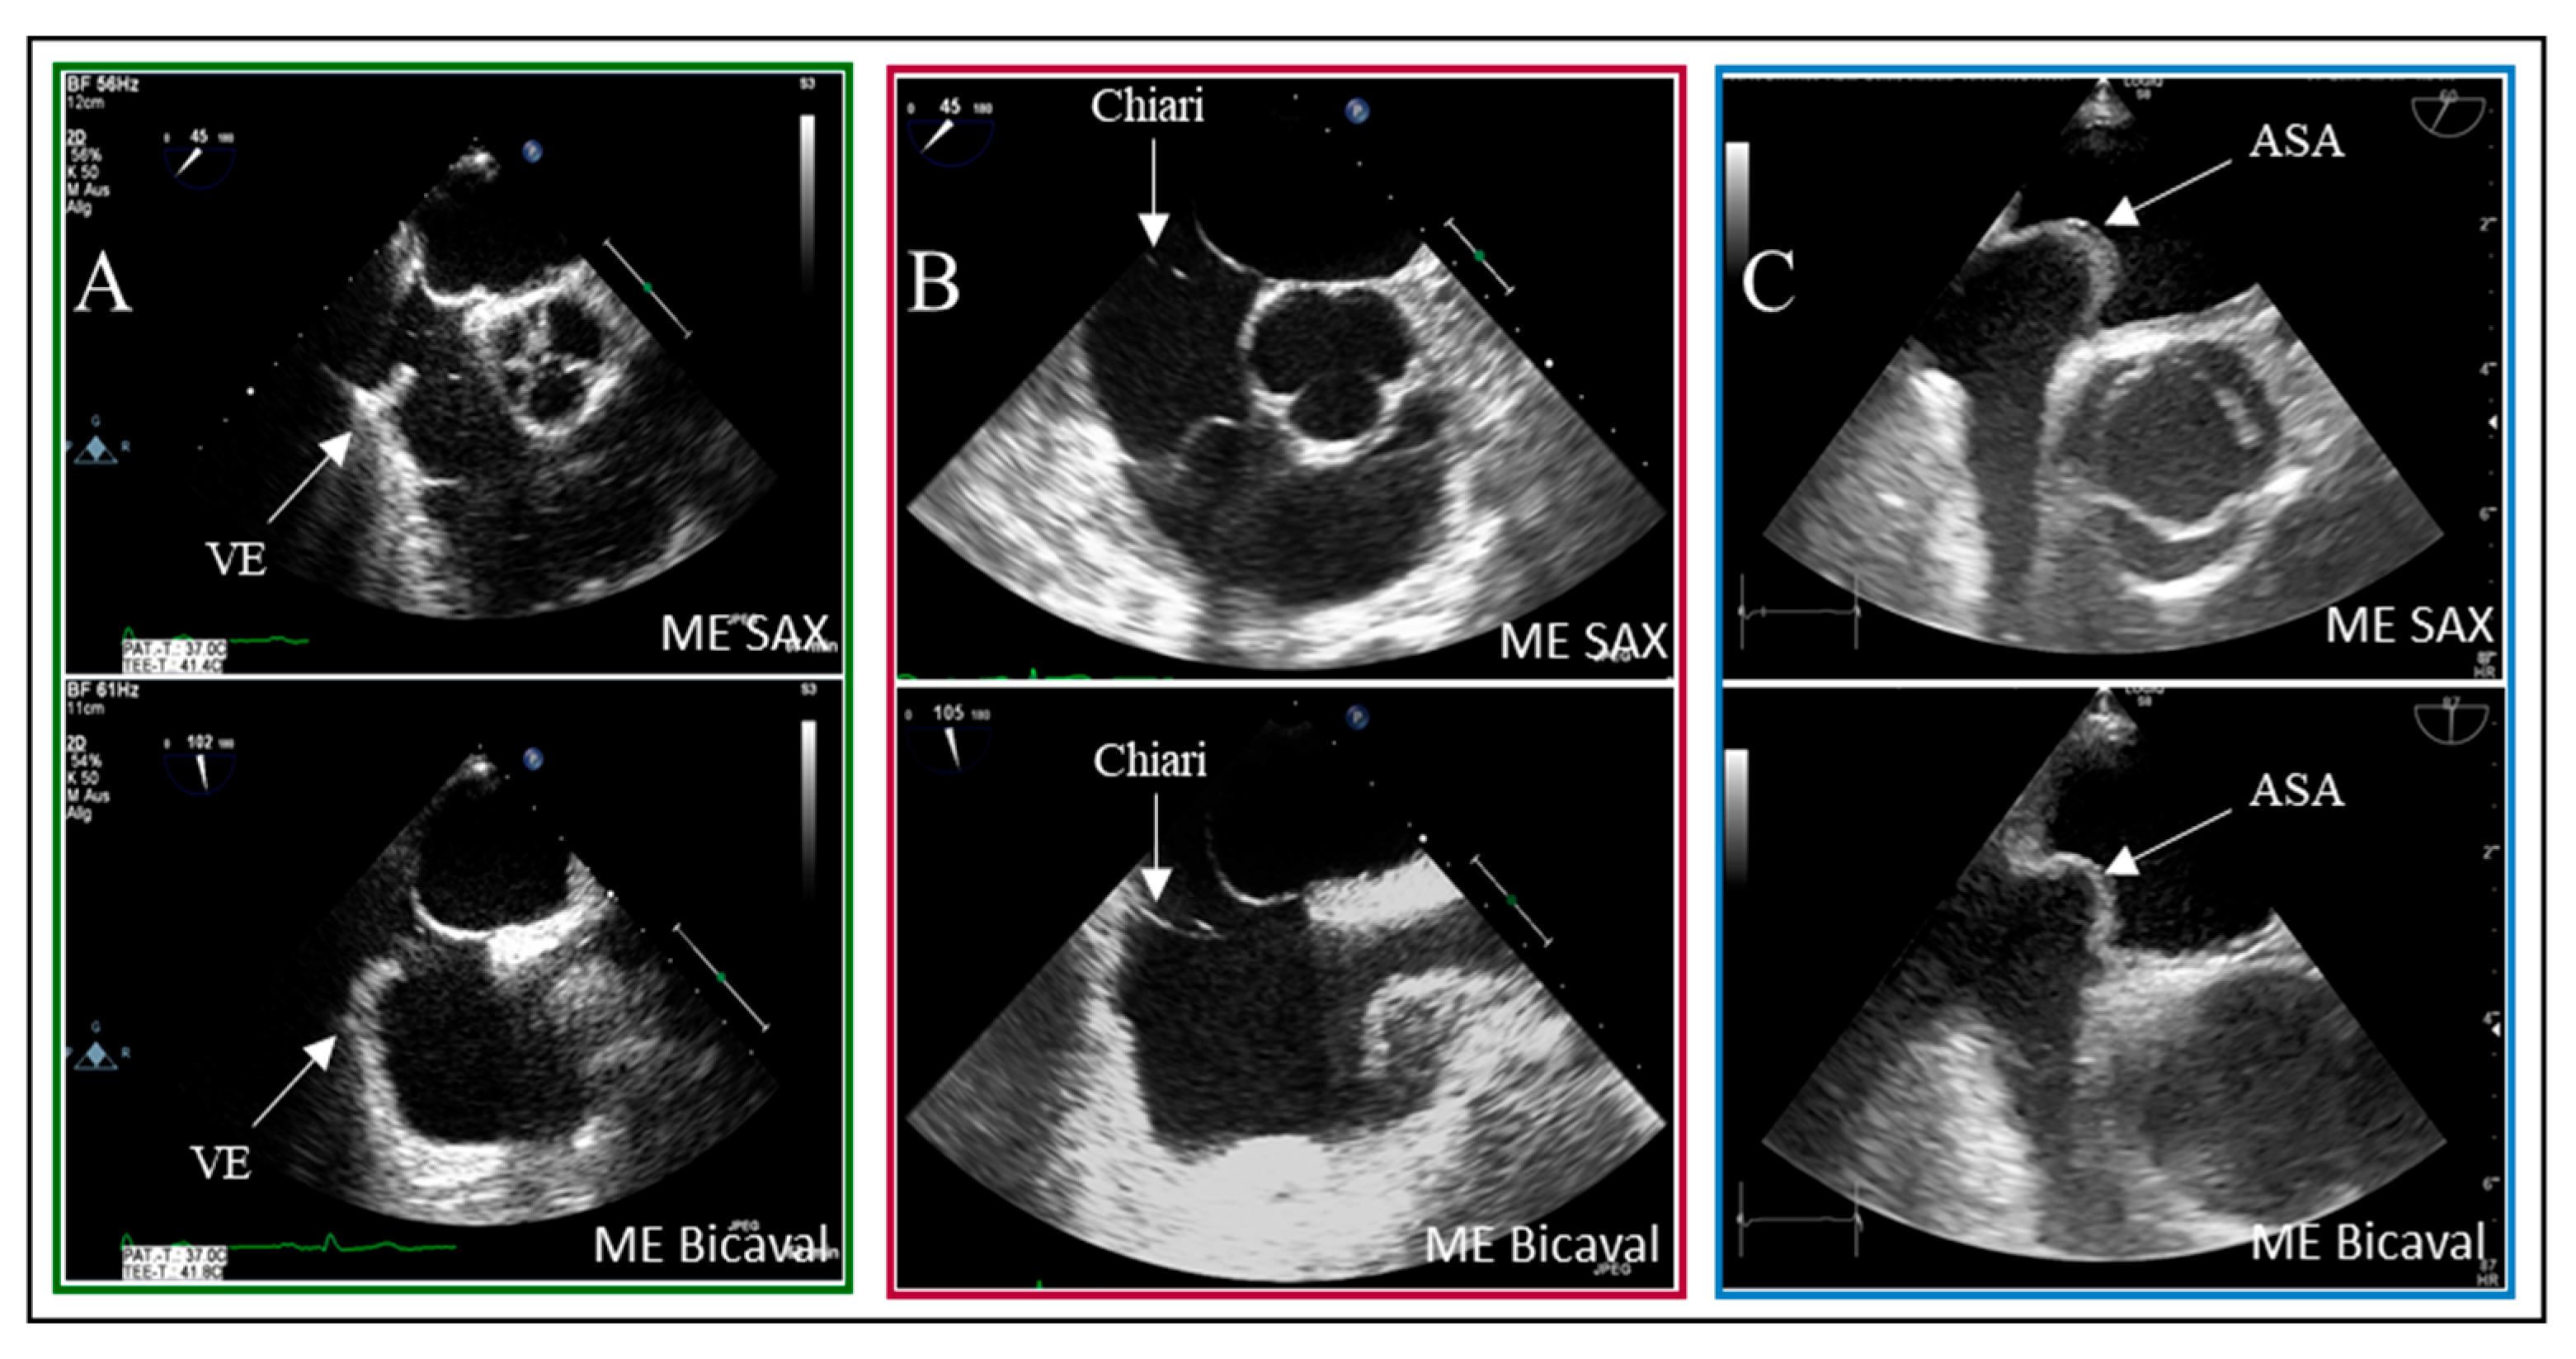

A structured approach could transform PFO diagnosis from a highly operator-dependent procedure into a reproducible, high-quality standard, particularly beneficial for less experienced operators. Given the results presented, we investigated whether precise quality indicators could enhance the reliability of PFO diagnosis in the context of transesophageal echocardiography (TEE). Standard TEE views demonstrating PFO shunting are shown in Figure 3.

Figure 3. Two-dimensional TOE recordings of an IAS with PFO. Shown is a short circuit between the RA and LA in ME 4CV, ME SAX, ME Bicaval image planes (A) in the color Doppler and (B) in the bubbles test; the red arrow indicates the direction of the short circuit. ME: midesophageal, SAX: short axis, 4CV: four chamber view, SP: septum primum, SS: septum secundum.